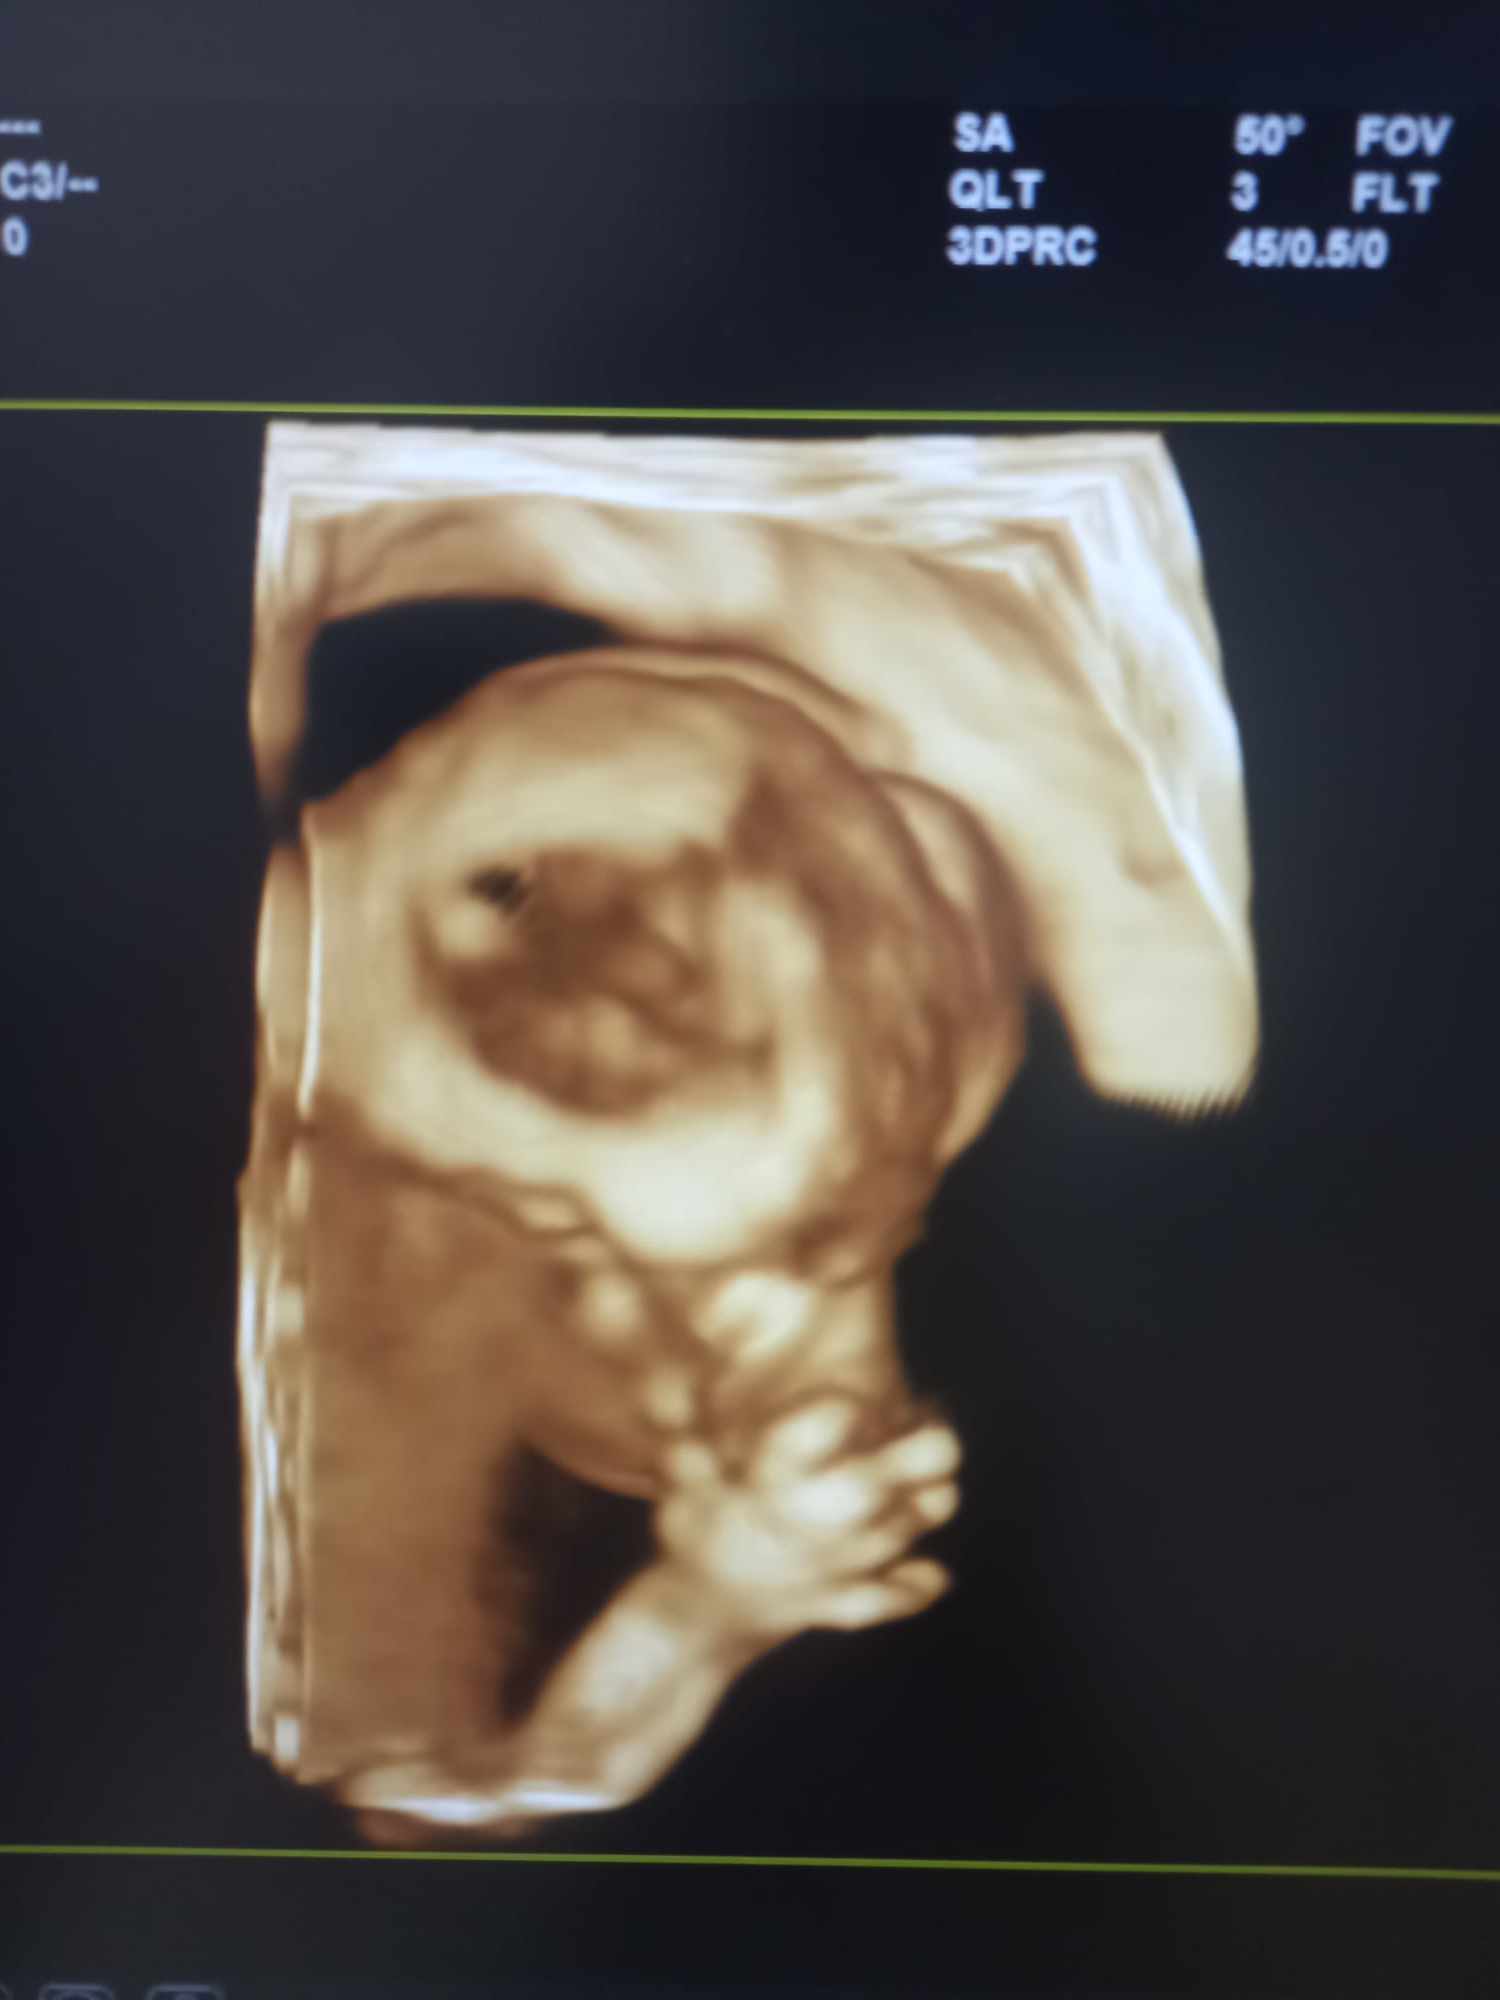

Pozrite si fotky z nášho moderného pracovného prostredia

Naša gynekologická ambulancia je vybavená modernou technikou a poskytuje pacientkom príjemné a komfortné prostredie pre všetky druhy vyšetrení a konzultácií.